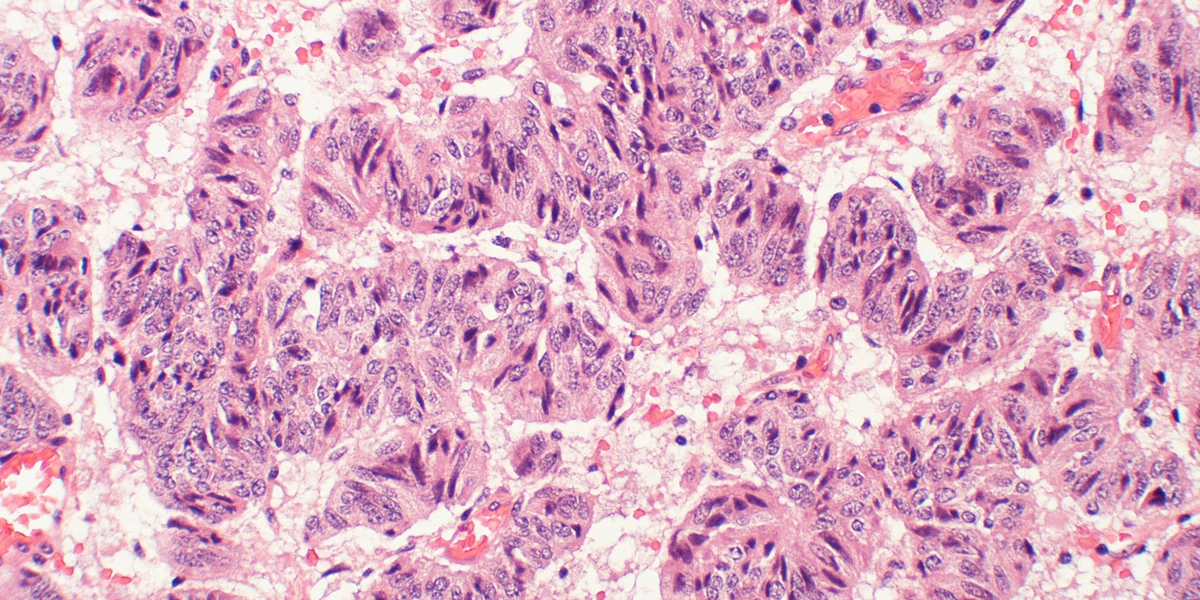

Typical carcinoid trabecular pattern